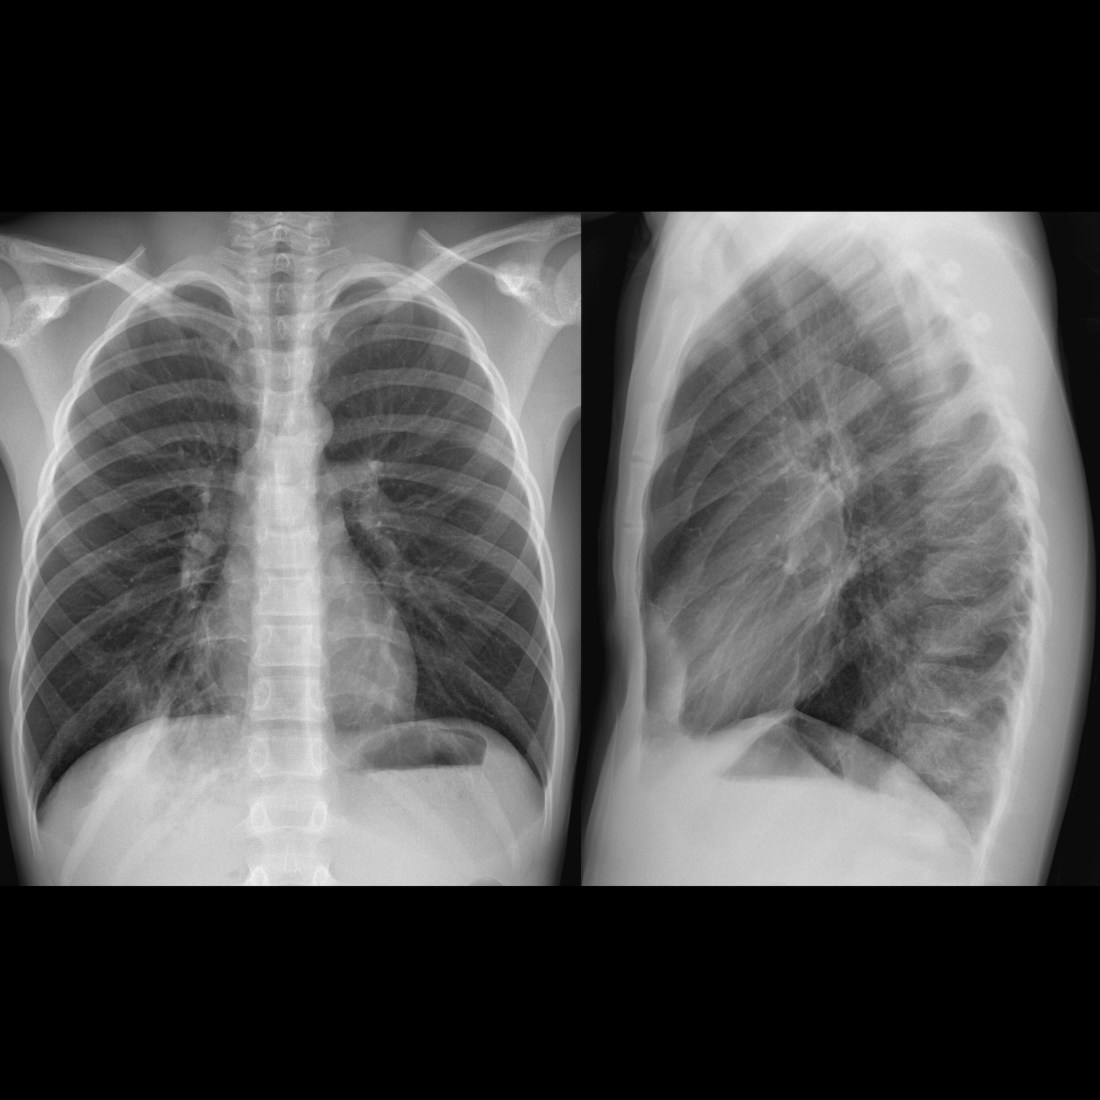

Zapalenie płuc na zdjęciu rentgenowskim ujawnia się przede wszystkim jako typowy obraz RTG przy zapaleniu płuc, z widocznymi zmianami w tkance płucnej. Obraz radiologiczny zależy od stadium choroby i patogenu, ale podstawowe są obszary zacienienia. Wczesne stadium może pokazywać jedynie nieostre zamglenie, w czasie gdy zaawansowane zapalenie objawia homogenne zagęszczenie.

Charakterystyczne infiltraty i konsolidacje w RTG płuc

Konsolidacja płucna, czyli konsolidacja płucna, stanowi podstawowy objaw i pojawia się jako jednorodne zacienienie zajmujące segment lub płat płuca. Na zdjęciu RTG widać wyraźne granice zmian, często z powietrznym bronchogramem – czarnymi oskrzelami na tle białego tła. W zapaleniu bakteryjnym, np. pneumokokowyminfiltraty są lobarne i zajmują dolne płaty w 70-80% przypadków. Zapalenie płuc na zdjęciu rentgenowskim może imitować atelektazę, ale obecność gorączki i leukocytozy pomaga w różnicowaniu.

Wirusowe zapalenia płuc pokazują obraz drzewa w pączku, z centralnym zagęszczeniem i otaczającymi go pasmami nacieków. Drobne guzki pęcherzykowe tworzą mozaikowy wzór, szczególnie w zapaleniu wywołanym Mycoplasma. Śródmiąższowe zapalenie objawia się liniami Kerleya lub siateczkowatym zagęszczeniem, bez dużych konsolidacji.